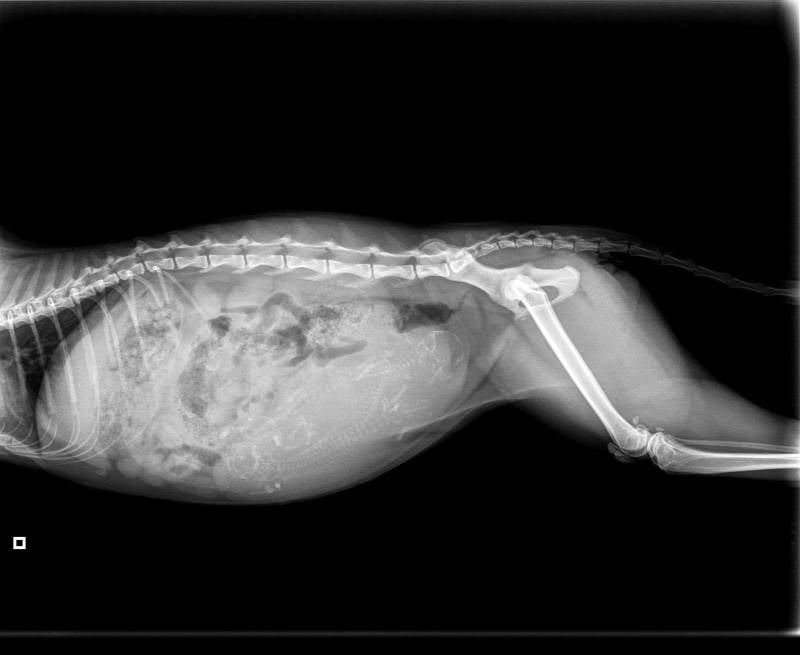

25-09-2017 65 dagen

Foto 22: 61 tot 65 dagen

Foetus bevindt zich in eindstadium in baarmoeder vanaf dag 59, vanaf deze dag zijn ze ook levensvatbaar met volgroeide organen, mocht moederpoes van ze bevallen. Voor deze dag hebben ze medische hulp nodig om te overleven. Ongeveer 12 tot 24 uur voor de bevalling daalt lichaamstemperatuur van aanstaande moederpoes.